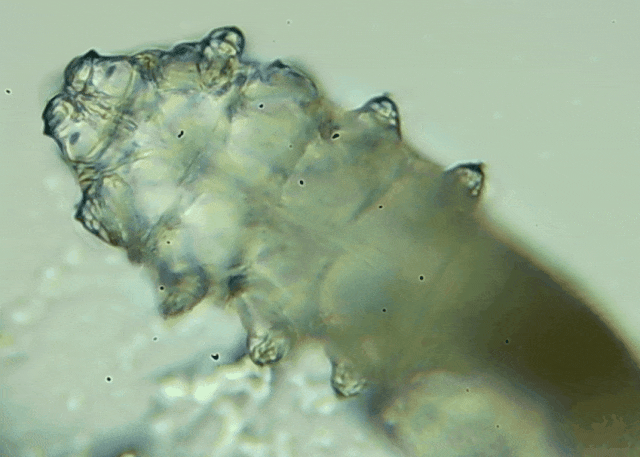

蠕形螨是一類肉眼看不見的寄生螨,常見的有毛囊蠕形螨和皮脂蠕形螨,常駐在人類的毛囊和皮脂腺里,尤其是眼睛的瞼板腺和睫毛根部。數量少時,蠕形螨能與人體“和平共處”,但一旦你免疫力下降、油脂分泌旺盛或清潔不到位,他們就會以你難以想象的速度瘋狂繁殖。